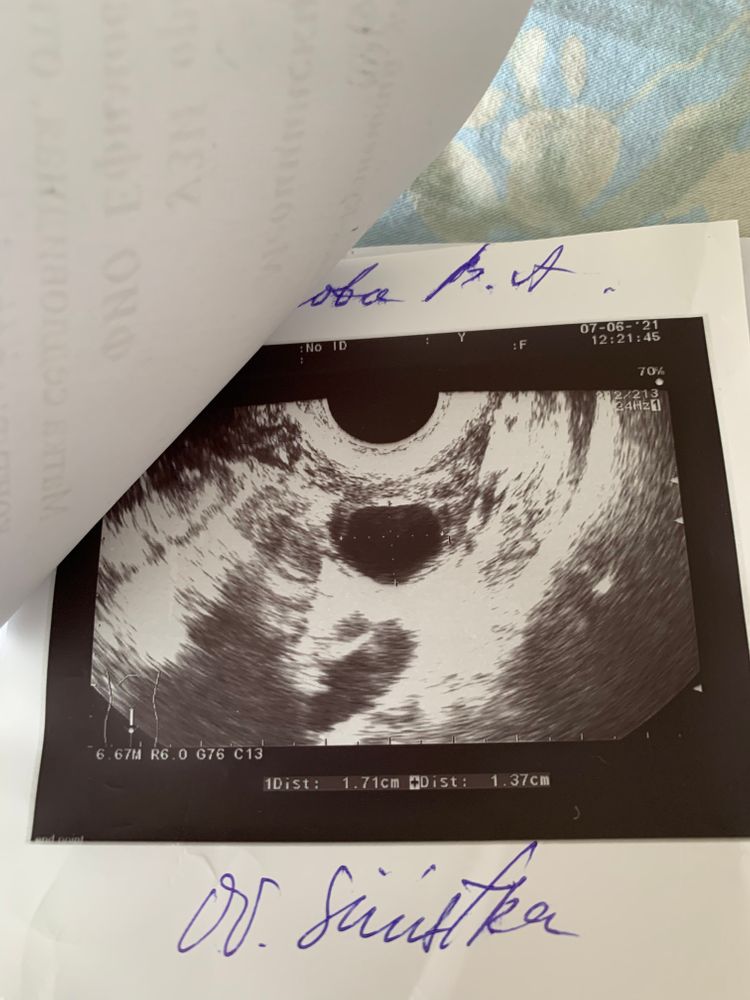

Всем привет. Можно ли ли по узи органов малого таза увидеть спаечный процесс?? Сегодня гинеколог сказала: другие может и не видят, а я увижу. Смотрю на узи и кажется там все в спайках((( нагоняю на себя. Страшно. Посмотрите☹️ самое страшное для себя услышать трубы непроходимы - только эко .

Вы анимии и витамины проверяли? Гормоны половые, щитовидной. Ну овуля получается есть, на узи ДФ 17мм в левом Я? Эндик всегда норм? Полипов, кист не находят? Циклы регулярные?